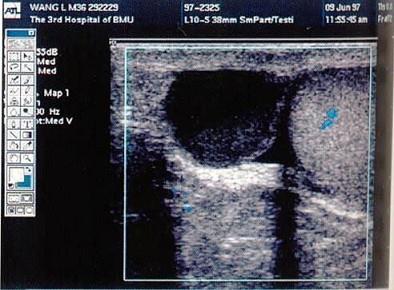

问题 患者,男,23岁,发现睾丸内无痛性肿块1月余。透光试验阳性。结合超声图像,最可能的诊断是?(?)

选项 A.睾丸囊肿 B.精索鞘膜积液 C.附睾结核 D.精液囊肿 E.附睾囊肿

答案 D